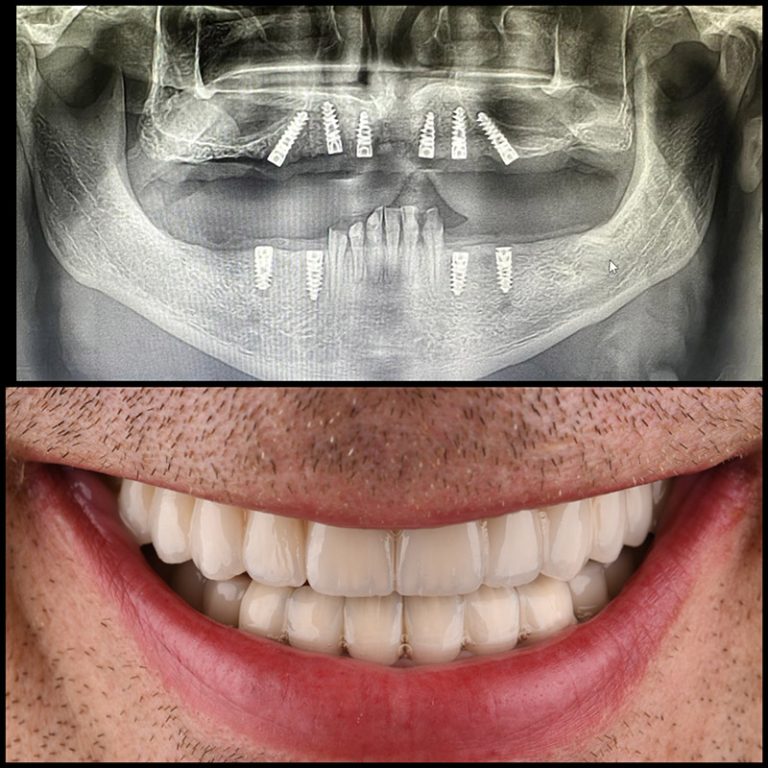

All on 4

All on 6

Kod potpune bezubosti, najefikasnije rešenje je proteza na implantatima.

Implantati služe kao stabilna osnova, a proteza može biti trajno fiksirana ili skidajuća, u zavisnosti od kliničkog slučaja.

Indikacija: potpuna bezubost